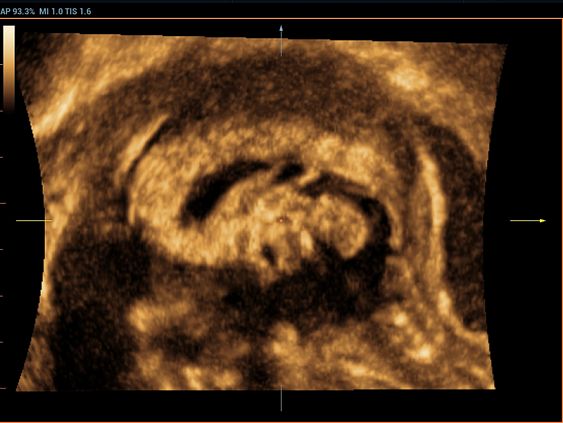

Клинические изображения

- Smart Planes

Благодаря уникальной новаторской технологии компании Миндрей, система Resona 6 является новейшей системой ультразвуковых исследований, обеспечивающей полностью автоматическое и точное получение особо важных проекций и проведение наиболее часто используемых измерений ЦНС плода, что обусловливает интеллектуальную диагностику, улучшение производительности и снижение зависимости от пользователя.

Smart Planes — это удобный для пользователя инструмент, значительно повышающий эффективность сканирования за счет увеличения точности в сочетании с автоматизацией работы. Одного нажатия на клавишу достаточно, чтобы из 3D данных, полученных при сканировании мозга плода, немедленно получить стандартные плоскости сканирования ЦНС: MSP (медиальная сагиттальная плоскость), TCP (трансцеребральная плоскость), TTP (трансталамическая плоскость) и TVP (трансвентрикулярная плоскость), а также получаемые в них измерения (БПР, ОГ, ЛЗР, Поперечный Диаметр Мозжечка, Большая Цистерна и Ширина Бокового Желудочка).